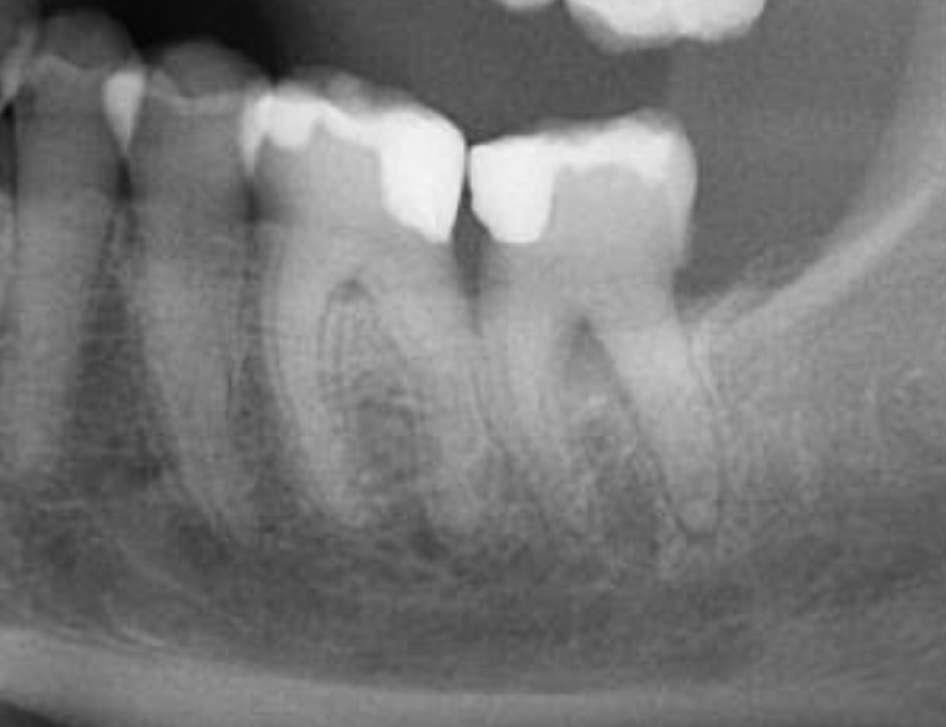

Die Patientin wurde zur Beurteilung und Behandlung von Zahn Nr. 46 an unsere endodontische Praxis überwiesen. Klinisch wies Nr. 46 eine Vollkeramikkrone auf, reagierte negativ auf Kälte und war empfindlich gegenüber Perkussion. Die präoperative Röntgenaufnahme ergab, dass Nr. 46 eine periapikale Radioluzenz an der distalen Wurzel und eine starken Krümmung der D-Wurzel im apikalen Drittel aufwies.

Vor der Operation

Es wurde ein Zugang zu Zahn Nr. 47 erstellt und die Kanäle MB, ML sowie DB und DL lokalisiert. Die Kanäle wurden mit EdgeFile X7-Rotationsfeilen mit einer Crown-DownTechnik instrumentiert.

Konuspassung

Die Arbeitslängen wurden mit dem Apex-Locator bestimmt, gefolgt von einer röntgenologischen Bestätigung. Das Kanalsystem wurde mit BUSA BC Sealer und BC GP Point verschlossen. Der Zugang wurde sofort mit einem faserverstärkten Dual-CureKernmaterial wiederhergestellt.

X7s 25.06 bis Widerstand, dann 20.06 bis Widerstand, dann 25.06 bis Widerstand. Arbeitslänge Handfeile bis 15, ggf. 17.04, 30.04, 35.04, 40.04. Für diesen Fall habe ich energisch Handfeilen über meine typische Reihenfolge hinaus bis zu einer #35K verwendet und abschließend mit einer X7 35.04 bei 500 U/min, 2,6 N/ cm Drehmoment gearbeitet.